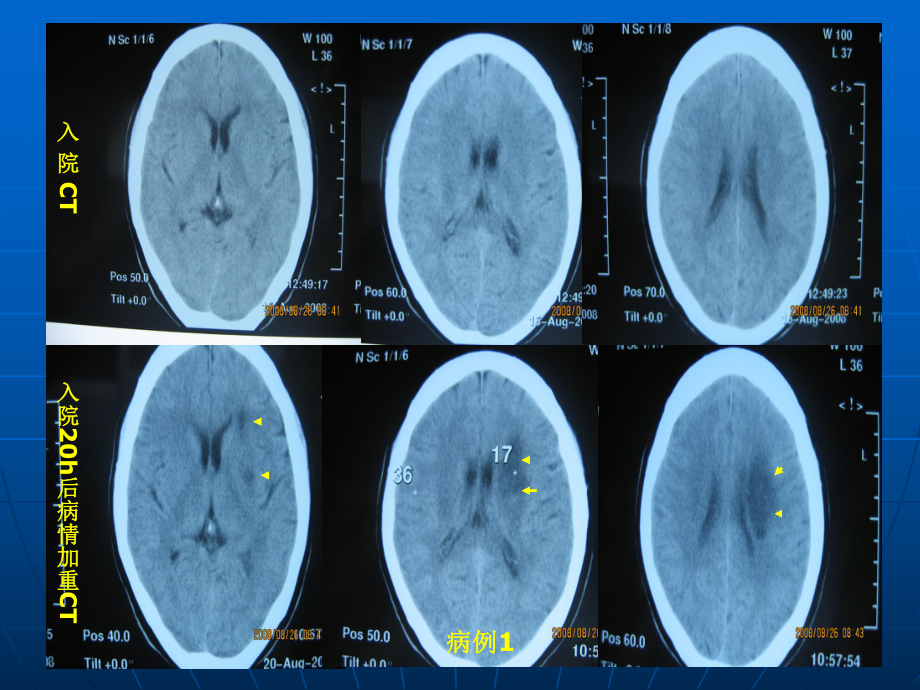

1、入入 院院 CT入院入院20h后病情加重后病情加重CT病例病例1病例病例2大脑皮质血管脑脑 表表 面面 血血 管管皮质动脉和髓质动脉皮质动脉和髓质动脉脑表面动脉深穿动脉深部微血管PCT示左额叶颞叶示左额叶颞叶MCA区区CBF下降和下降和CBV升高,升高,MTT和和TTP明显延长提示血流动力学异常明显延长提示血流动力学异常 SPECT示示ACA-MCA分水岭区低灌注分水岭区低灌注双侧性皮质前、后型双侧性皮质前、后型CWI粥样斑块伴出血残留管腔粥样斑块ICA狭窄狭窄血栓栓子附壁血栓附壁血栓脱落栓子脱落栓子ACAMCACWI卵圆孔未闭卵圆孔未闭房颤房颤心梗心梗主动脉弓粥样硬化主动脉弓粥样硬化颈动脉粥

7、前动脉脉络膜前动脉Arteria basilaris BA 基底动脉供临床供临床WSI分析用脑动脉供血区模板分析用脑动脉供血区模板入入 院院 CT入院入院20h后病情加重后病情加重CT病例病例1 左侧皮质下上型左侧皮质下上型WSI类似病例分析类似病例分析病例病例2 右侧皮质前型右侧皮质前型WSI病例病例3 右侧皮质前、后和上型右侧皮质前、后和上型WSI皮质前型皮质前型皮质后型皮质后型皮质上型皮质上型DSACTA颈动脉内膜剥脱术颈动脉内膜剥脱术颈动脉支架置入术颈动脉支架置入术n单侧ICA病变常引发同侧半球梗死。Chen等对62例同侧颈动脉重度狭窄所致急性脑梗死的发病机制和梗死类型进行的研究显示,